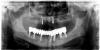

Wasja Опубликовано 29 декабря, 2012 Поделиться Опубликовано 29 декабря, 2012 Контрольное орто, временные коронки на винтах установлены через 3 дня. Ссылка на комментарий

pit Опубликовано 29 декабря, 2012 Поделиться Опубликовано 29 декабря, 2012 (изменено) Контрольное орто, временные коронки на винтах установлены через 3 дня.По Rg снимкам - все красиво, что касается фоток- над ними надо работать.Можно несколько вопросов.1. Сколько имплантатов было нагружено?2. Какая была фиксация?3. Есть ли фото временной конструкции на модели?4. В 4-ом секторе что-то планируется? Изменено 29 декабря, 2012 пользователем pit Ссылка на комментарий